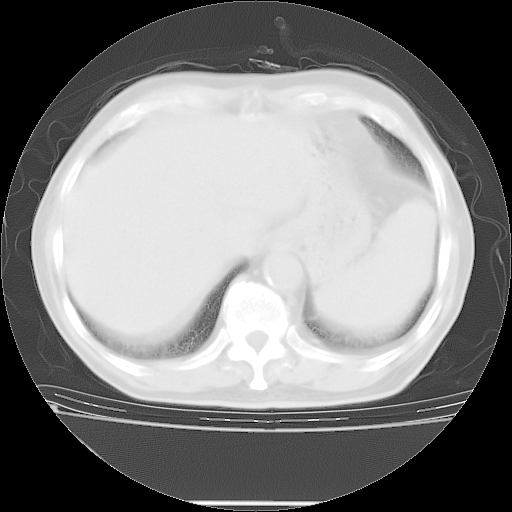

今天复查肺部CT,发现双肺广泛磨玻璃样改变。所以我把3月19日和5月9日相隔50天的肺部CT上传。请大家会诊。

2009年3月19日肺部CT片。

2009年3月19日肺部CT